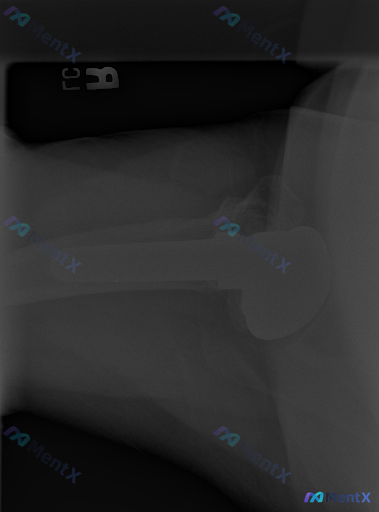

整理到一份影像资料:左侧肩关节置换术后的腋位(Cross-table)X光片。 先看这份影像的客观描述: - 人工肱骨头假体及柄部位置良好,未见明显松动、断裂或透亮带 - 盂肱关节对位正常,无脱位/半脱位 - 假体周围骨质密度均匀,未见溶骨性破坏或明显骨赘 - 周围软组织轮廓基本正常,无明显钙化 影...